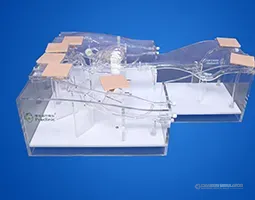

Radial Artery Puncture Operation Model (Ultrasound Guided) adalah simulator lengan bawah untuk pelatihan kanulasi arteri radialis dengan panduan USG. Arteri radialis dibuat berdasarkan data CT manusia.

Material komposit khusus memungkinkan visualisasi arteri yang jelas di layar USG *real-time*. Memberikan sensasi ‘tembus’ (*breakthrough*) yang realistis saat jarum menembus dinding arteri.

Drawing of Radial Artery Puncture Operation Model (Ultrasound-Guided)